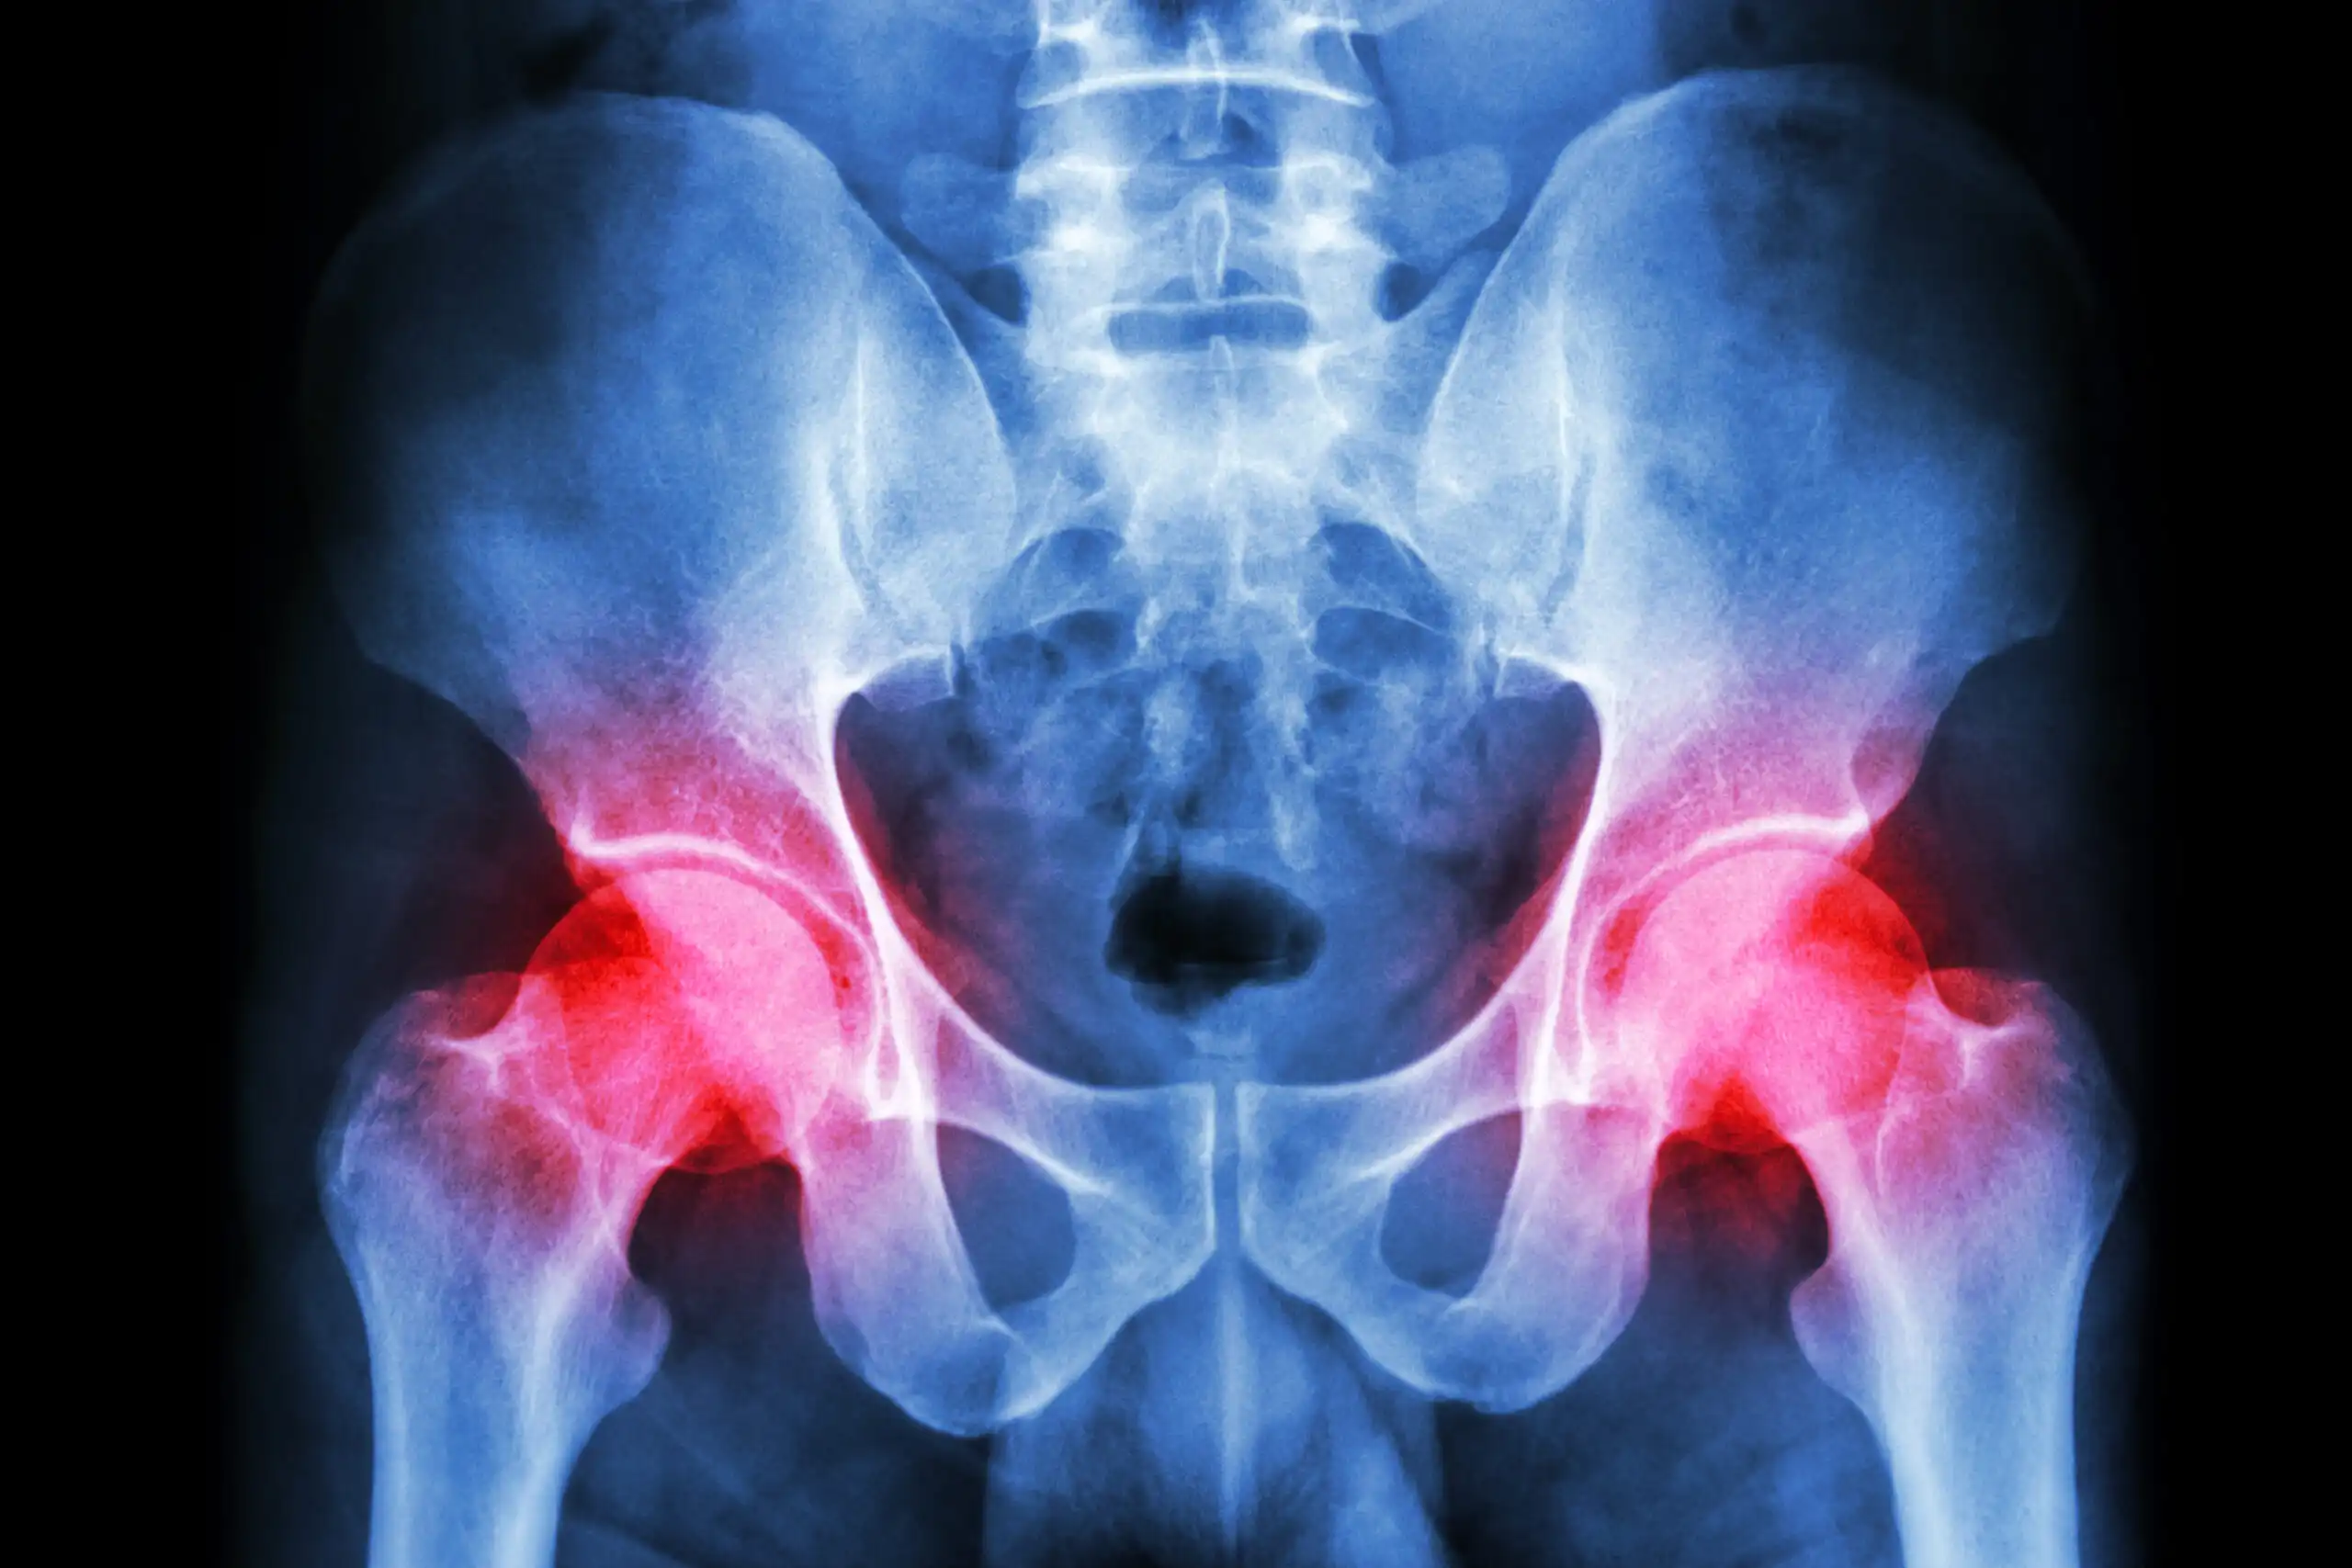

درد مفاصل و استخوانها آزارتان میدهد؟

تعویض مفصل لگن

جراحی تعویض مفصل لگن، یکی از موفق آمیزترین روش های جراحی است که با هدف تسکین درد و بهبود دامنه حرکتی بیمار انجام می شود ...